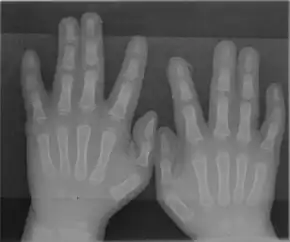

Radiograph of Type 1 syndactyly of the hands (no bony involvement)

Five types[3] of syndactyly have been identified in humans. The corresponding loci associated with these types and their common phenotypical expression are as follows:

• type I: 2q34-q36;[4] webbing occurs between middle and ring fingers and/or second and third toes.